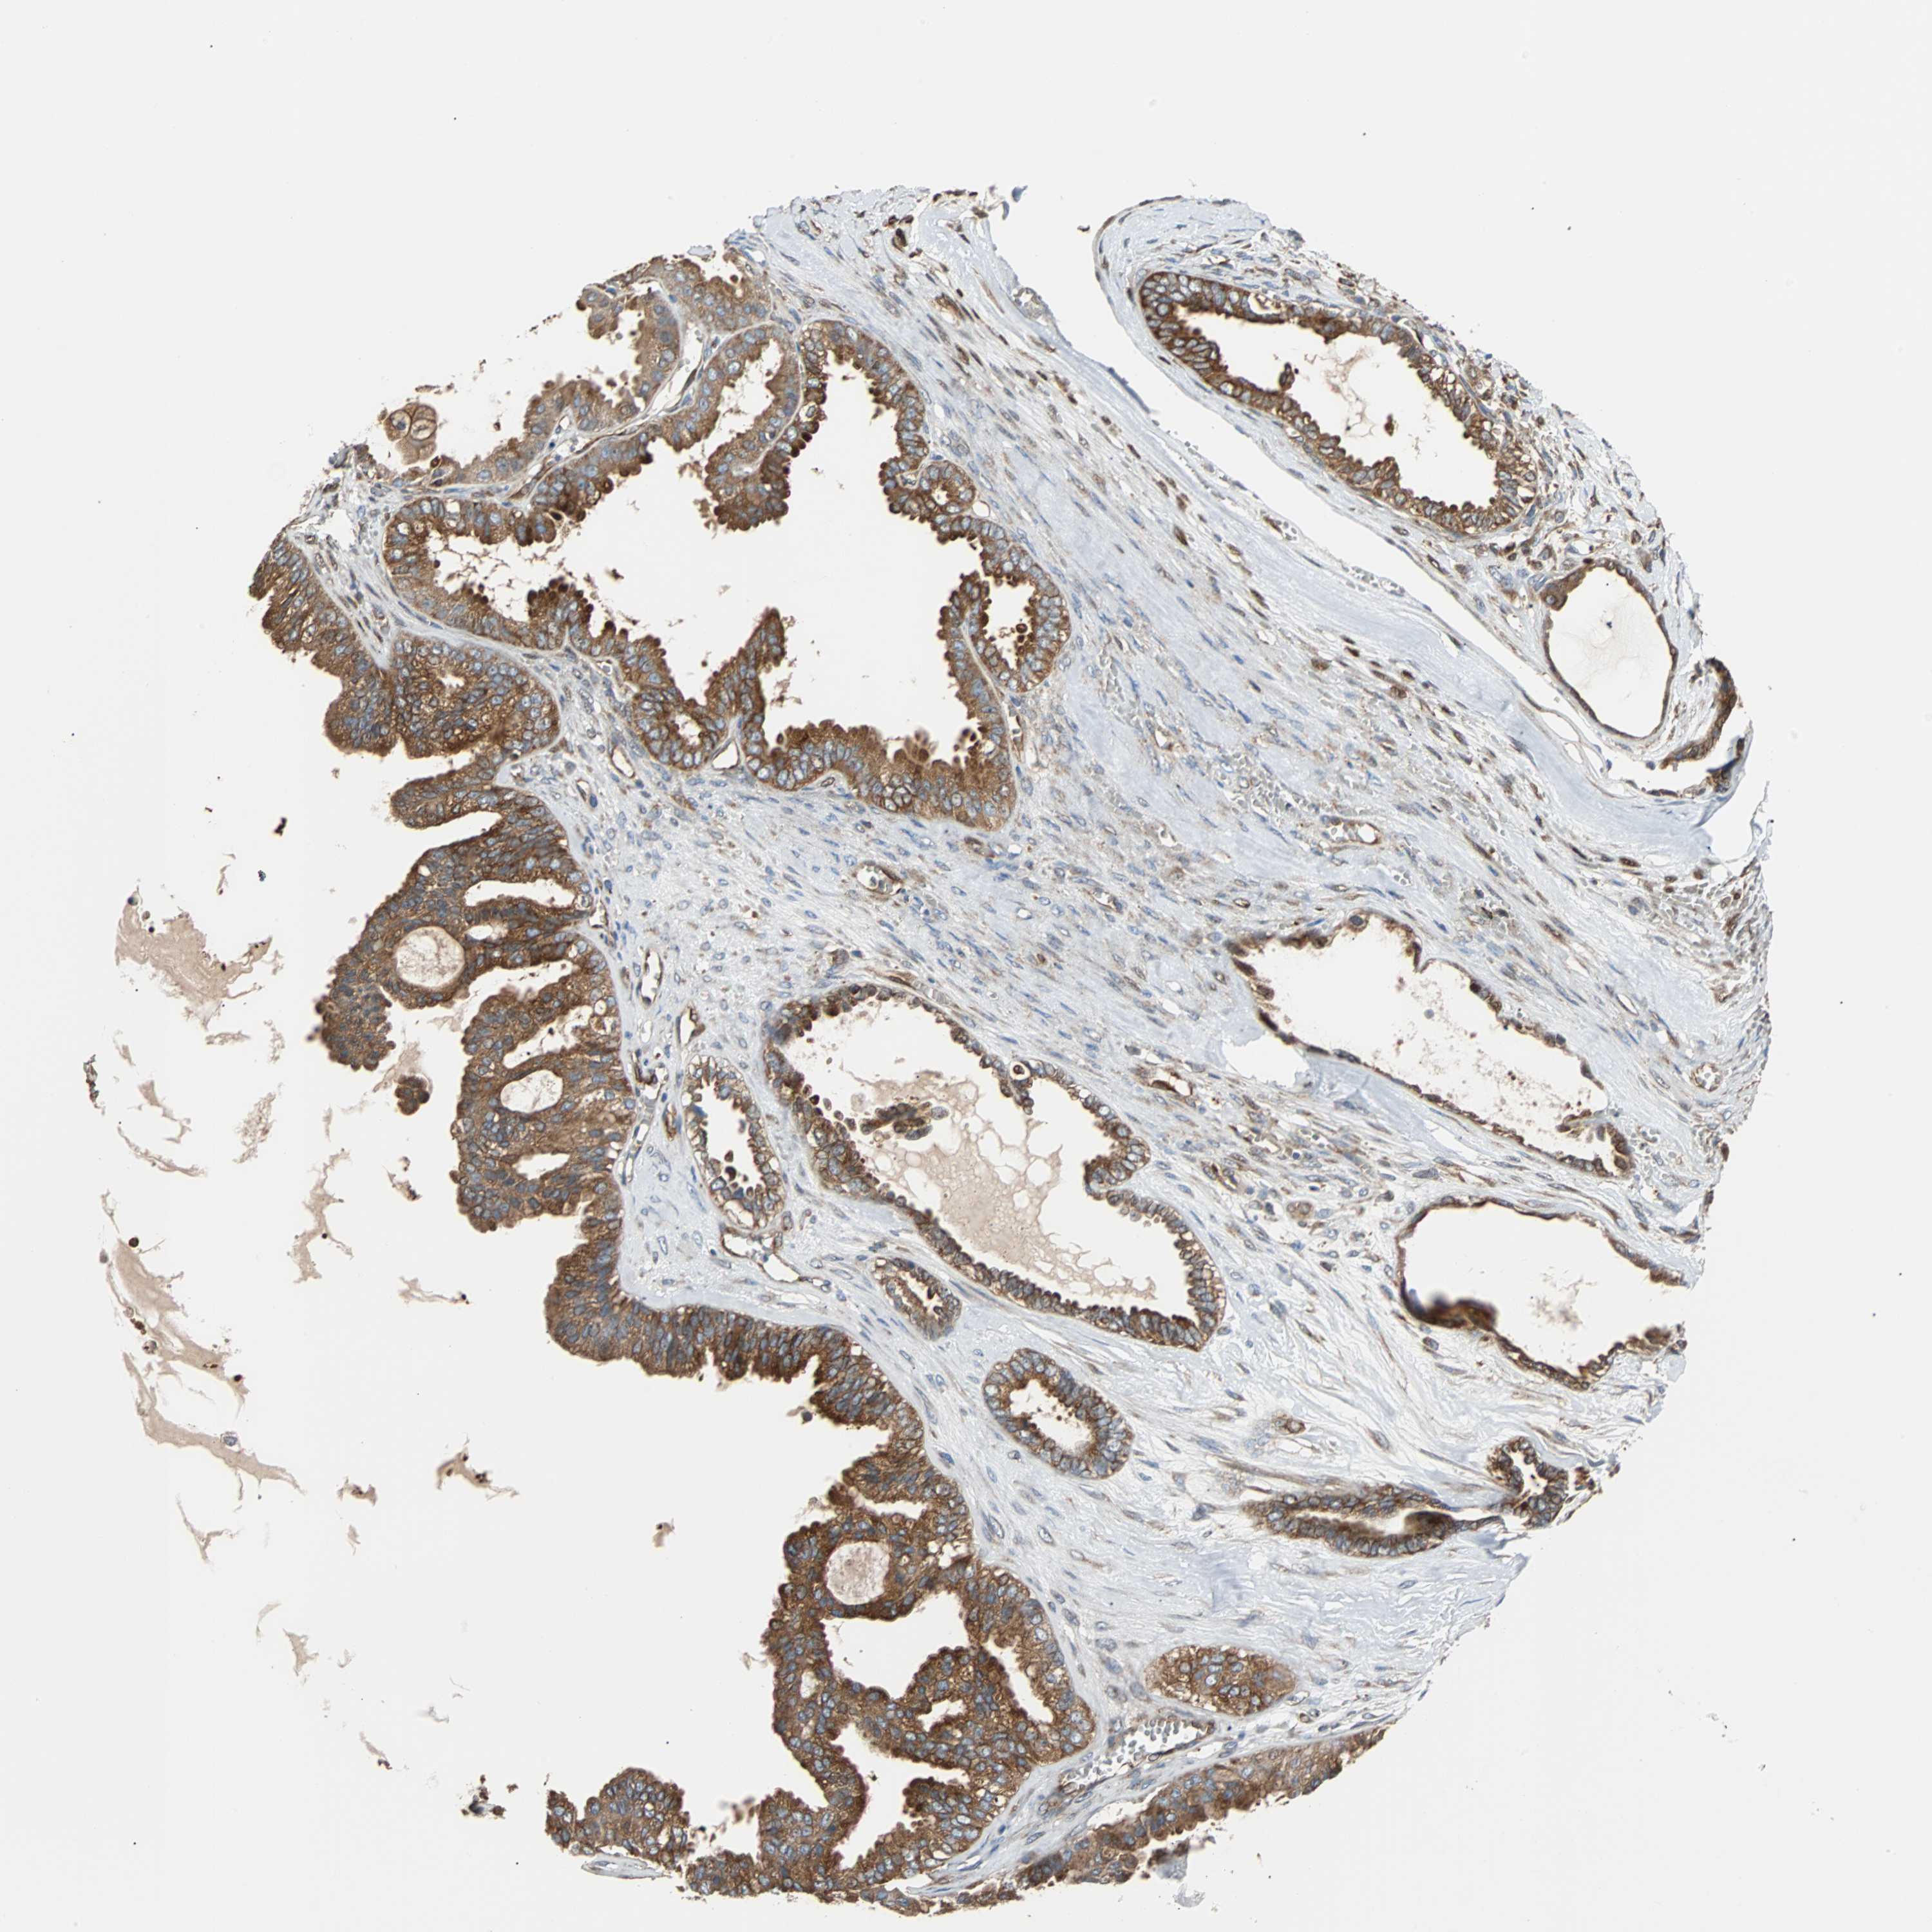

OVARIAN CANCER - Protein expressioni

A mouse-over function shows sample information and annotation data. Click on an image to view it in a full screen mode. Samples can be filtered based on level of antibody staining by selecting one or several of the following categories: high, medium, low and not detected. The assay and annotation is described here.

Note that samples used for immunohistochemistry by the Human Protein Atlas do not correspond to samples in the TCGA dataset.

Antibody stainingi

Antibody staining in the annotated cell types in the current human tissue is reported as not detected, low, medium, or high, based on conventional immunohistochemistry profiling in selected tissues. This score is based on the combination of the staining intensity and fraction of stained cells.

Each image is clickable and will lead to virtual microscopy that enables deeper exploration of all samples and also displays staining intensity scores, fraction scores and subcellular localization as well as patient and tissue information for each sample.

Antibody CAB004264

Antibody CAB005030

Staining

High

Cystadenocarcinoma, serous, NOS

Carcinoma, endometroid

Carcinoma, NOS

Cystadenocarcinoma, mucinous, NOS